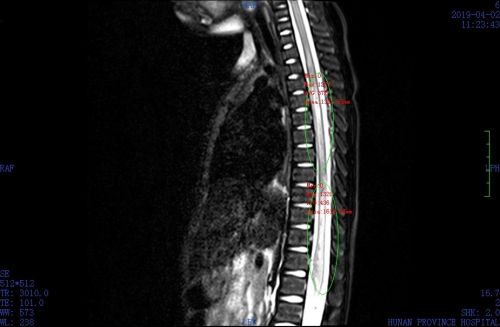

核磁共振显示,琦琦胸段、腰段脊髓损伤。

心急如焚的家长立马将琦琦送往长沙,辗转多家捷克论坛 后,住进捷克论坛 小儿骨科。在此过程中,家长为了安抚女儿,一直把她抱在手中。16日凌晨入住小儿骨科后,护士立即让琦琦平卧在硬板床上,接受进一步观察和治疗。接诊医生表示,孩子胸段、腰段脊髓损伤严重,双下肢肢体感觉、运动功能都受到影响,需进行消肿、脱水、止血、营养神经以及高压氧、针灸等治疗。